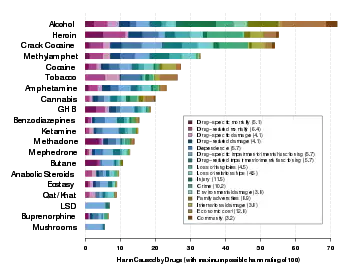

The causal relationship between alcohol consumption and cardiomyopathy and heart failure is unclear.[2] Per the American Heart Association (AHA), alcohol is one of the leading causes of dilated cardiomyopathy.[2] However, multiple longitudinal studies have shown a paradoxical lowering of dilated cardiomyopathy with modest-to-moderate alcohol consumption.[2]

Interestingly, in patients that are defined as "heavy drinkers" (defined as consuming >30g of alcohol/day) decreased alcohol consumption to moderate levels has been shown to be an effective treatment; in fact [12] A retrospective cohort study analyzed data collected from over 3.8 million patients, and categorized patients as either abstinent drinkers, mild drinkers, moderate drinkers, and heavy drinkers. Despite having such a large sample size, the association between alcohol intake and cardiomyopathy remains unclear.[12] The study found that patients that were either mild or moderate drinkers were the least likely to develop HF as compared to patients that were abstinent.[12] The study also found that patients that increased their alcohol consumption from light to moderate and/or from moderate to heavy were at increased risk for heart failure.[12] Although one might think that patients that were completely abstinent from alcohol would have would be least likely of being diagnosed with heart failure, it's actually patients categorized as either light or moderate drinkers had the lowest risk for developing HF.[12]